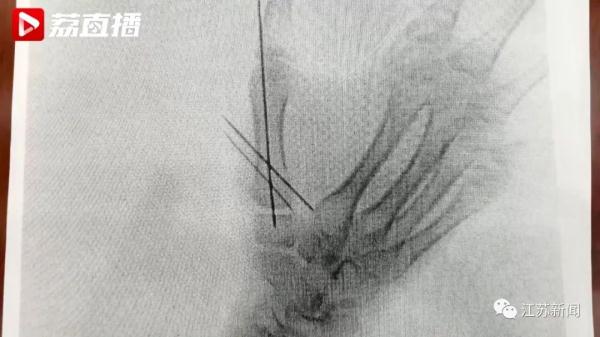

“在这个过程中,由于情节过于暴力和血腥,我的女儿又担任了里面最危险的角色‘牺牲者’,导致她手掌骨骨折。”原告父亲黄先生说。

黄先生称,孩子受伤后,曾要求中止游戏,但商家没有同意。孩子的4名同学也因游戏过于恐怖受了皮外伤。